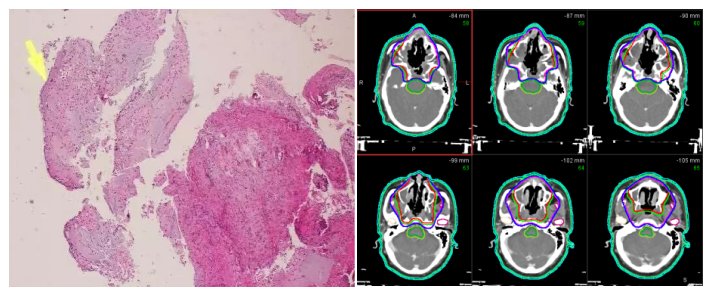

Figure 1 Pathology Figure 2 Target Delineation